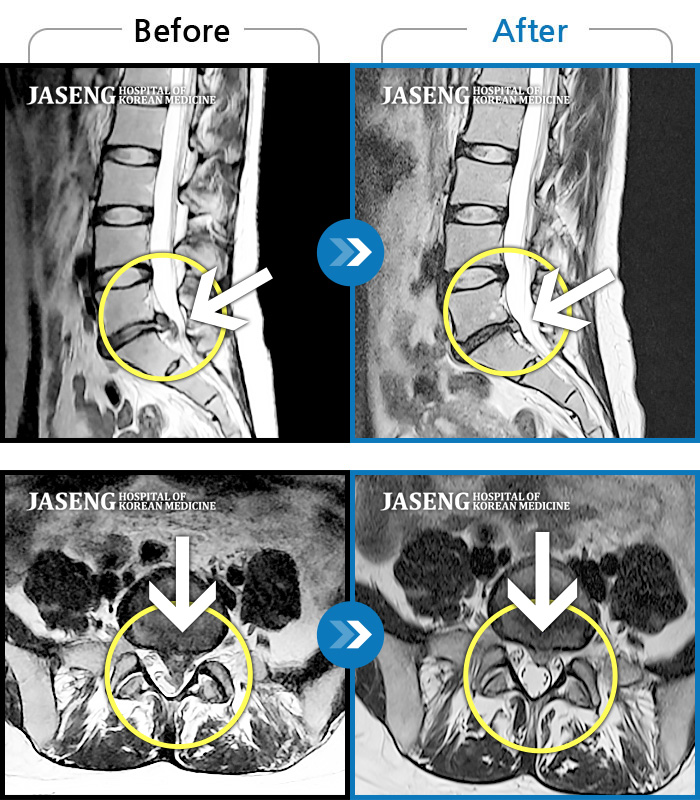

허리디스크

광주 · 김동은 원장

허리 양측 둔부에서 발가락으로 통증, 비증, 힘이 빠지는 증상

촬영시기

2018.08.11 ~ 2019.03.27

2019.04.25

조회수 18,502